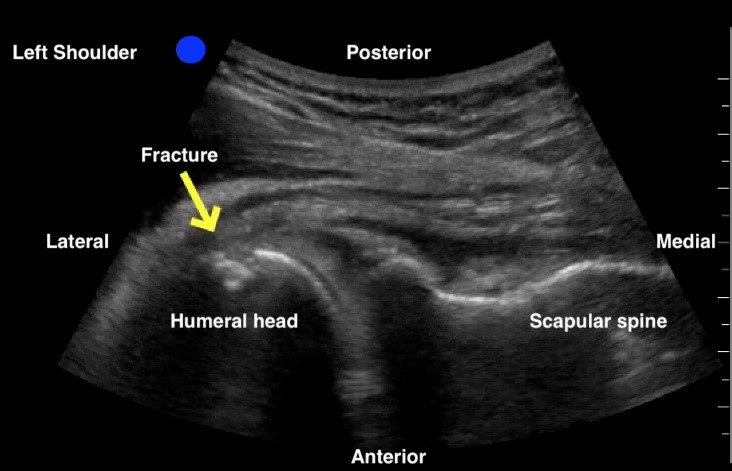

An anterior shoulder dislocation will show the humeral head displaced to the far field region of the screen, while the posterior dislocation will show the humeral head displaced to the near field region (Figures 3 and 4). A shoulder subluxation will show the humeral head partially sliding (or “dislocating”) in and out of the GHJ with shoulder movement (Figure 5). While less accurate, POCUS can also help identify fractures, such as the Hill-Sachs, the Bankart, or a humeral head fracture (Figure 6).

Figure 4: Non dislocated left humeral head fracture. Humeral head and neck fracture confirmed on plain x-ray